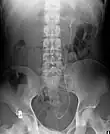

Ureteral stents are used to ensure the patency of a ureter, which may be compromised, for example, by a kidney stone. This method is sometimes used as a temporary measure to prevent damage to a kidney caused by a kidney stone until a procedure to remove the stone can be performed.

An ureteral stent it is typically inserted using a cystoscope, and one or both ends of the stent may be coiled to prevent movement. Ureteral stents are used for various purposes, such as temporary measures to prevent damage to a blocked kidney until a stone removal procedure can be performed, providing drainage for compressed ureters caused by tumors, and preventing spasms and collapse of the ureter after trauma during procedures like stone removal. The thread attached to some stents may cause irritation but allows for easy removal by pulling gently. Stents without threads require cystoscopy for removal. Recent developments have introduced magnetic retrieval systems that eliminate the need for invasive procedures like cystoscopy when removing the stent. The use of magnets enables simple extraction without anesthesia and can be done by primary care physicians or nurses rather than urologists. This method has shown high success rates across different patient groups including adults, children, and kidney transplant patients while reducing costs associated with operating room procedures.